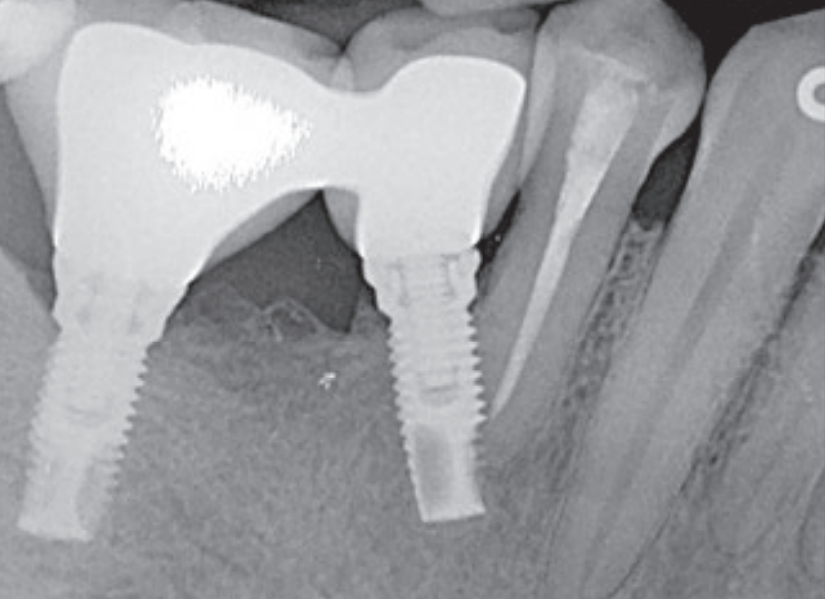

1周后临床检查显示#44牙髓活力测试(冷测)无反应,确诊牙髓坏死。患者转诊至牙体牙髓科行根管治疗,2周后X线检查发现根尖区透射影。术后2个月,#46位点种植体出现松动伴脓性渗出,诊断为早期失败,予以取出并行手动清创(配合0.12%氯己定冲洗)。同期对#45位点种植体完成二期手术(图2a)。

3个月后,于原失败位点(#46)植入新MK III Brånemark种植体(常规平台,10mm),同期影像显示种植体就位良好(图2b)。